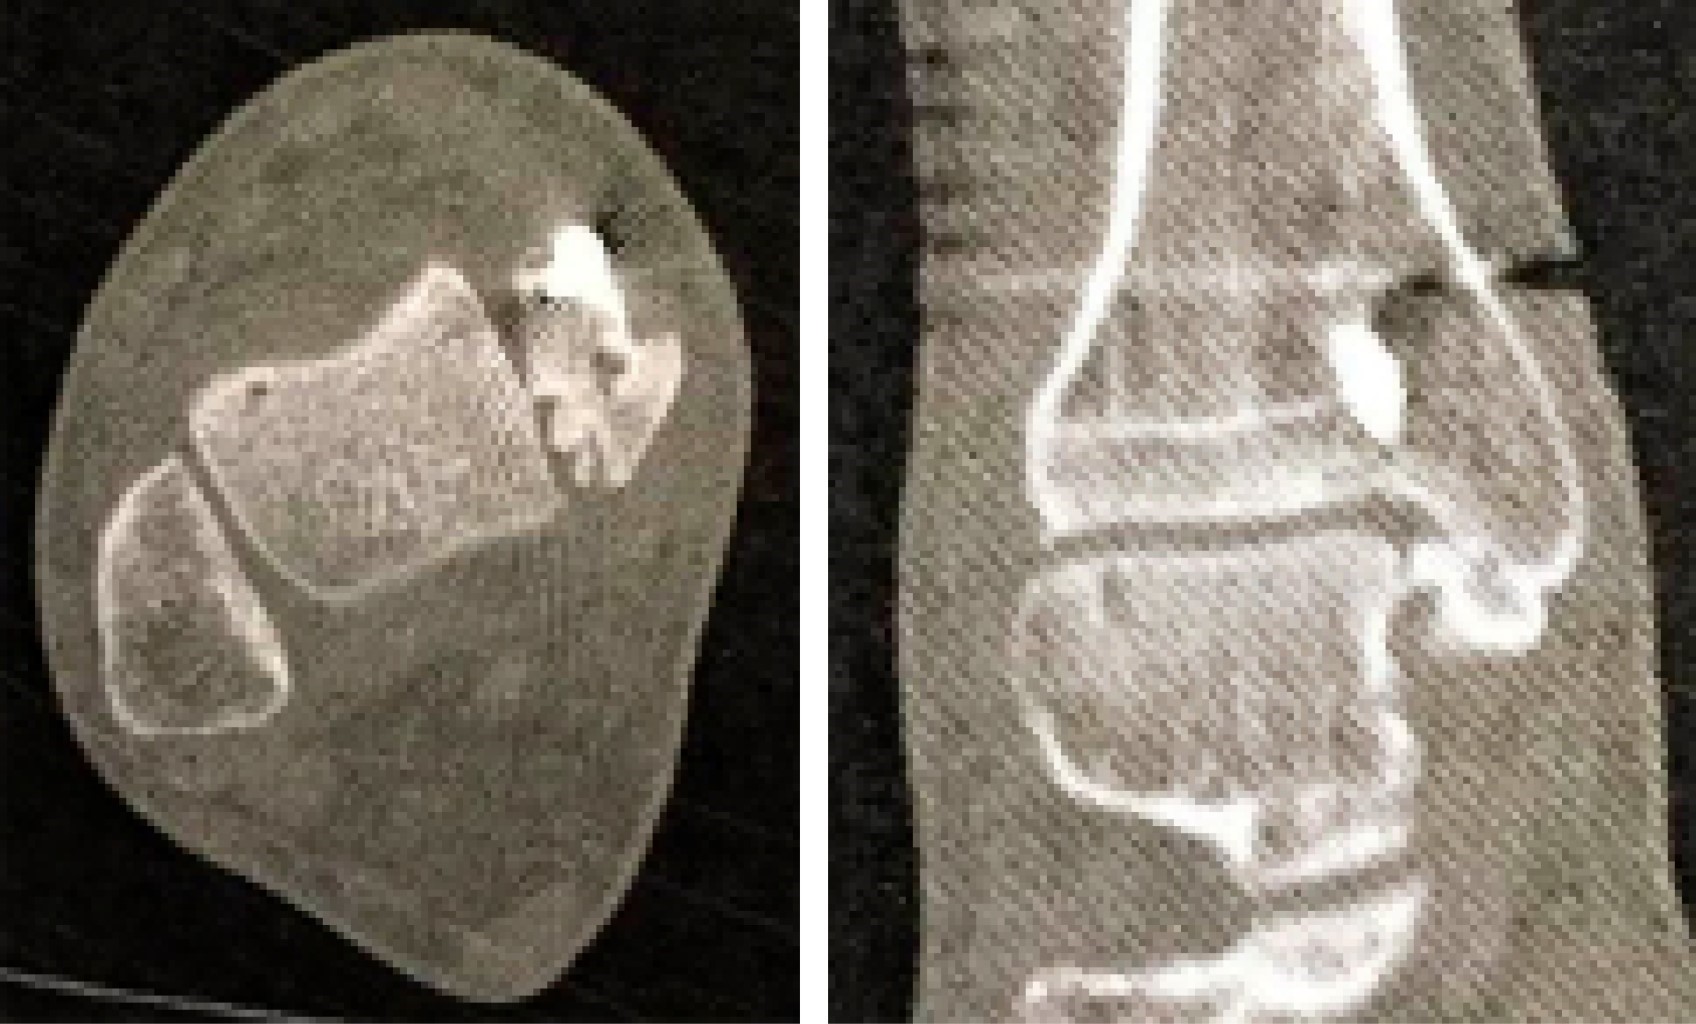

The CT Scan confirmed a medial malleolus rotational malunion with a bone fragment that blocked the ankle dorsiflexion. There was also a talar lateral translation causing tibiotalar incongruency and syndesmosis malreduction, with diastasis (Figure 3).

In our first case, the irregularity of the internal medial malleolus facet did not allow for a correct assessment of the medial clear space. The tibiofibular clear space was apparently greater than 5 mm (abnormal), but the tibiofibular overlap was not accurate for measurement because it was unclear if the radiograph was a strict ankle AP or mortise view. The CT Scan was important to show the transverse plan anatomy and allowed us to see the rotational and sagittal translation of the fibula, as opposed to only diastasis on the coronal plane.